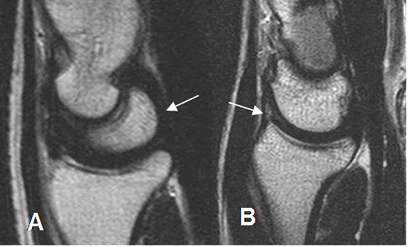

Los ligamentos también son bien estudiados con la RM. El grupo de intrínsecos es mejor visualizados en secuencias coronales y los extrínsecos en cortes sagitales. (4). Se identifican como estructuras delgadas, con baja señal de intensidad (SI) en todas las secuencia, adyacente a estructuras óseas y rodeados por grasa. (Fig 24 a 27).

Fig 24. Ligamentos intrínsecos normales.

A: RM coronal en T1, B: RM coronal en STIR y C: RM coronal en GE.

Ligamento escafolunado (Flecha delgada) y ligamento semilunopiramidal (Flecha gruesa).

Fig 25. Ligamentos extrínsecos anteriores normales.

A: RM coronal en GE Ligamento radioescafoideo.

B: RM coronal en T1. Ligamento radiolunopiramidal.

Fig 26. Ligamentos extrínsecos posteriores normales.

A: RM coronal en T2. Ligamento radioescafoideo.

B: RM coronal en GE. Ligamento radiolunado.

C: RM coronal en T2. Ligamento radiopiramidal.

Fig 27. Ligamentos normales.

A: RM sagital en T2. Ligamento radioescafogrande.

B: RM sagital en T2. Ligamento radioescafoideo posterior.